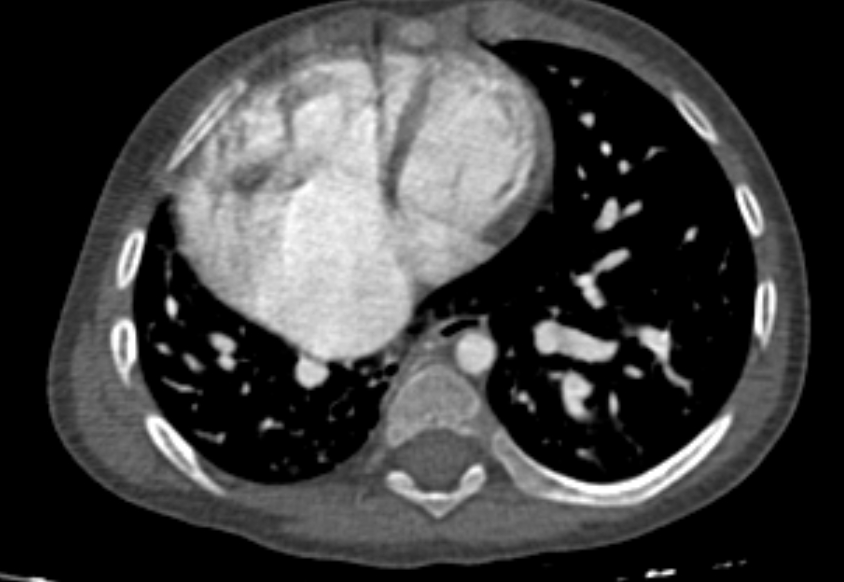

• On CT looks like a tension pneumothorax without the collapsed lung

• Case courtesy of Husam Hussein Yaseen, Radiopaedia.org, rID: 75133